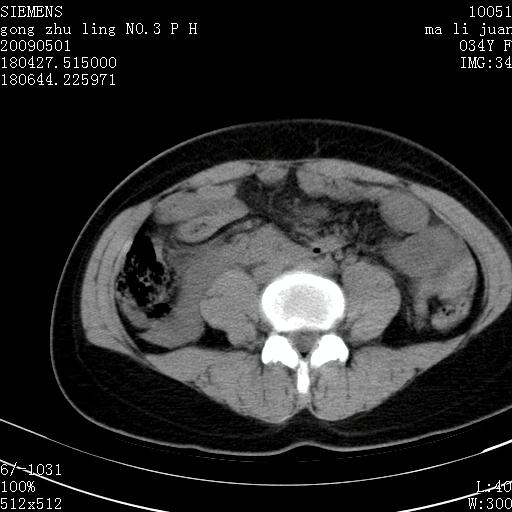

标题: CT19733:右肾碎裂

青年女性,骑摩托车摔伤。

右肾碎裂伤,包膜下血肿。

术中仅见右肾碎裂,肾蒂血管未见断裂。

支持 右肾破裂伴肾包膜下及肾周血肿。

右肾破裂并右侧腹膜后间隙出血。